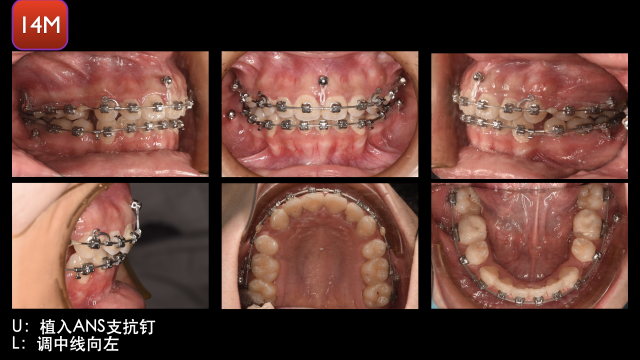

术中治疗